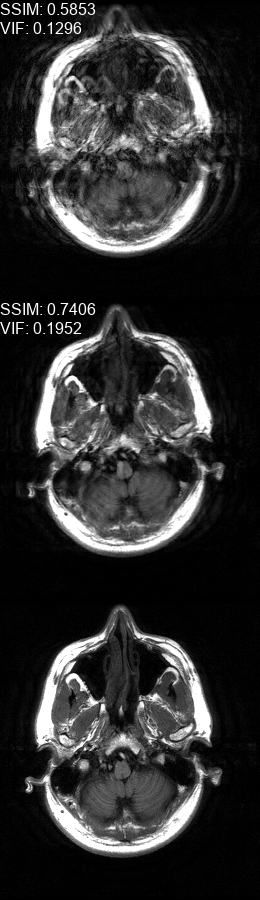

Results  Experimental results using the two presented datasets, for the fully-sampled and under-sampled k𝑘k-space scan orders, are shown in Table 1. The table presents the Normalized Mean Square Error (NMSE) obtained for each of the scan orders. For the Transaxial dataset, we only show the results for the challenging task where the DP contains only up to 707070 columns of k𝑘k-space data. All methods are able to reduce the NMSE of the corrupted scans, however the methods that incorporate the DC layer achieve a much better result. These results match our subjective visual impression of the motion-corrected images, as may be seen in Fig. 3 for simulated motion in a fully-sampled k𝑘k-space data, and Fig. 4 for an under-sampled k𝑘k-space data.

Refer to caption

(a)

(b)

(c)

(d)

(e)

(f)

Figure 4: Motion corrected images from the Diverse dataset calculated using the 𝒰𝒮260𝒰subscript𝒮260\mathcal{US}_{260} scan order presented in Fig. 1c. The bottom row shows the fully-sampled motion-free images. The top row shows the under-sampled motion-corrupted images used as input to the correction method, these images show an additional aliasing artefacts in comparison to the ones in the top row of Fig. 3 since they are missing approximately half of the k𝑘k-space data. The middle row shows the corrected images calculated using our method. (a) contains two motions at t1=79subscript𝑡179t_{1}\!=\!79, t2=132subscript𝑡2132t_{2}\!=\!132, (b) contains a motion at t1=61subscript𝑡161t_{1}\!=\!61, (c) contains a motion at t1=83subscript𝑡183t_{1}\!=\!83, (d) contains two motions at t1=78subscript𝑡178t_{1}\!=\!78, t2=123subscript𝑡2123t_{2}\!=\!123, (e) contains three motions at t1=13subscript𝑡113t_{1}\!=\!13, t2=97subscript𝑡297t_{2}\!=\!97, t3=127subscript𝑡3127t_{3}\!=\!127, (f) contains two motions at t1=55subscript𝑡155t_{1}\!=\!55, t2=128subscript𝑡2128t_{2}\!=\!128.